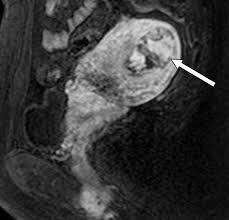

The latter four entities are referred to as gestational trophoblastic neoplasia GTN. A common characteristic of all gestational trophoblastic disease is an abnormal proliferation of trophoblast but different components predominate in different tumors. Ultrasound remains the radiological investigation of choice for initial. Gestational trophoblastic neoplasia GTN encompasses a broad spectrum of placental lesions from the pre-malignant hydatidiform mole complete and partial through to the malignant invasive mole choriocarcinoma and rare placental site trophoblastic tumour PSTT. The latter four entities are referred to as gestational trophoblastic neoplasia GTN. There are several histologically distinct types of GTD that range from premalignant complete and partial hydatidiform moles HMs to malignant diseases also known as gestational trophoblastic. Ultrasound in the Diagnosis and Management of GTN Gestational trophoblastic neoplasia GTN includes invasive mole choriocarcinoma PSTT and ETT. Because it is an unusual and serious disease that affects women of reproductive age as well as because its appropriate treatment results in high cure rates it is crucial that radiologists be familiar with gestational trophoblastic disease in order to facilitate its early diagnosis and to ensure appropriate follow-up imaging. Gestational trophoblastic disease GTD is a spectrum of both benign and malignant gestational tumors including hydatidiform mole complete and partial invasive mole Choriocarcinoma placental site trophoblastic tumor and epithelioid trophoblastic tumor.

Gestational trophoblastic disease GTD encompasses a heterogeneous group of lesions including hydatidiform mole invasive mole choriocarcinoma and placental site trophoblastic tumor Mazur and Kurman 1994. The term gestational trophoblastic disease GTD encompasses a spectrum of tumors with a wide range of biologic behavior and potential for distant metastases. Gestational trophoblastic disease GTD is a term used for a group of pregnancy-related tumours. GTD refers to both the benign and malignant entities in the spectrum and includes hydatidiform mole complete and partial invasive mole choriocarcinoma placental site trophoblastic tumor PSTT and epithelioid trophoblastic tumor ETT. There are several histologically distinct types of GTD that range from premalignant complete and partial hydatidiform moles HMs to malignant diseases also known as gestational trophoblastic. Ultrasound in the Diagnosis and Management of GTN Gestational trophoblastic neoplasia GTN includes invasive mole choriocarcinoma PSTT and ETT. GTD refers to both the benign and malignant entities in the spectrum and includes hydatidiform mole complete and partial invasive mole choriocarcinoma placental.